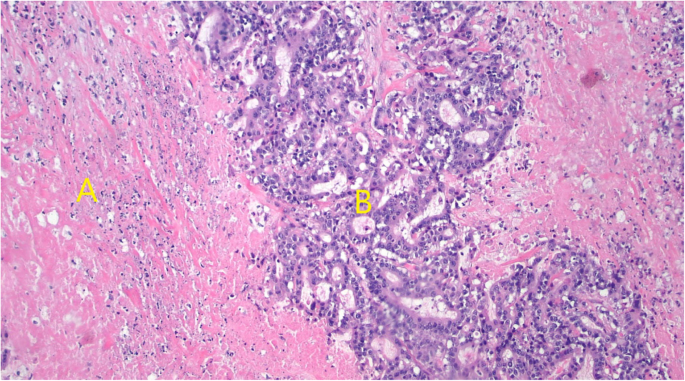

The patient is a 63-year-old man with a history of smoking, COPD, and stage 1 urothelial cancer who presented with a 3-month history of epigastric abdominal pain, early satiety, fatigue, and 12-pound weight loss. Esophagogastroduodenoscopy (EGD) demonstrated a large posterior body gastric ulcer (Fig. 1), and biopsies revealed poorly differentiated adenocarcinoma based on microscopic features. Differential included metastatic urothelial cancer versus a more likely primary gastric cancer. Negative stains for CK20, PSA, PSAP, Uroplakin II, chromogranin, synaptophysin, CK7, and CD56, a weak GATA-3 stain and positive stains for AE1/AE3 confirmed a diagnosis of a new primary gastric cancer (Fig. 2). Endoscopic ultrasound revealed many abnormal lymph nodes in the celiac region (level 20), peripancreatic region, and porta hepatis (largest measuring 9 mm by 5 mm) such that he was staged as a T3N3M0 by EUS criteria. PET scan revealed an FDG avid gastric mass. CT chest, abdomen, and pelvis and PET were negative for distant metastasis (Fig. 1).

Pathology revealed an 8.3 cm, poorly differentiated adenocarcinoma with invasion into the pancreatic parenchyma and histologically negative margins. Thirty-one regional lymph nodes were negative for metastasis making his final stage ypT4b N0 M0, Stage III. His post-operative course was uneventful. There was evidence of treatment effect related necrosis on final pathology indicating response to his neoadjuvant chemotherapy (Fig. 3).